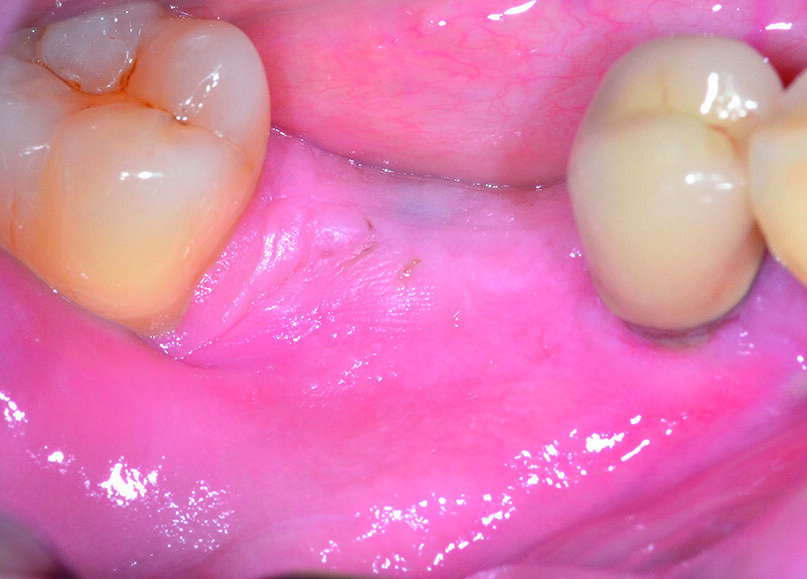

Al momento del controllo a 8 mesi vengono esaminate le condizioni dei tessuti parodontali marginali e si effettua una radiografia endorale periapicale, che evidenzia la completa risoluzione del difetto intraosseo (Figg. 17, 18). Incidentalmente, in occasione della scopertura dell’impianto precedentemente inserito, si sceglie di constatare de visu la rigenerazione ottenuta intorno all’ elemento 4.5: al sollevamento del lembo è possibile apprezzare la completa risoluzione del difetto intraosseo circonferenziale, a conferma di quanto già emerso dal controllo radiografico (Figg. 19, 21). Dopo aver esposto la testa dell’impianto in zona 4.6 si rimuove la vite di copertura, che viene sostituita con un healing abutment di adeguate dimensioni (Figg. 22, 23).

Nella stessa seduta operatoria, allo scopo di aumentare l’ampiezza e lo spessore dei tessuti periimplantari, viene quindi eseguito un lembo a scivolamento apicale associato ad un innesto di matrice collagenica tridimensionale in alternativa a un prelievo di tessuto connettivo dalla volta palatina: dopo aver posizionato il lembo apicalmente alla cresta ossea, si procede alla sutura a punti staccati con filo riassorbibile 6/0 (Figg. 24, 25).